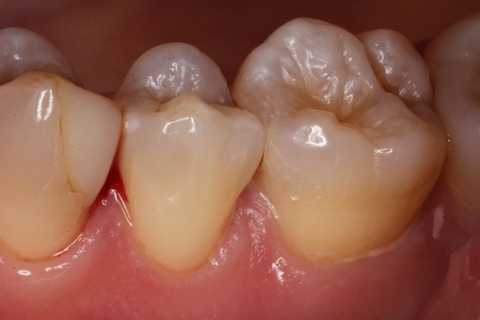

20代女性、右上6、咬合性外傷による隣接面カリエス

この歯は10年以上も削らずに様子を見ていたのだが、最近しみるようになったとかで、東京住まいだし、次帰れるのは年末か?コロナもあるし分からない、、ということなので、介入することにした。

実像から